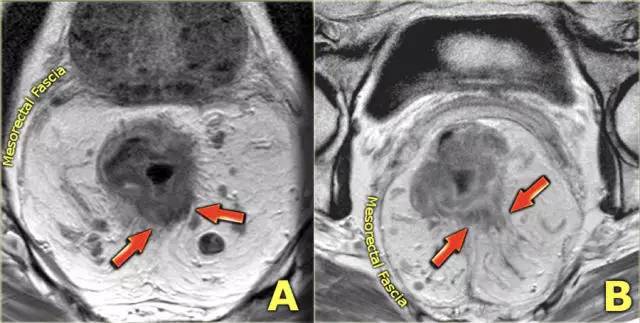

图 6 T3 直肠癌 MRF-,肿瘤浸润直肠系膜,1~4 点钟位置

图 7 直肠周围浸润(左);肿瘤局限于肠壁(右)